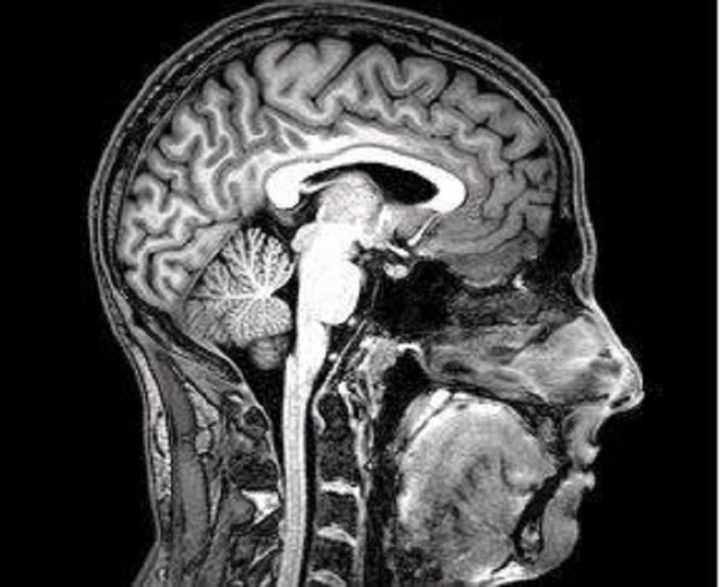

Los pacientes infectados con coronavirus que han recibido terapia con oxígeno y experimentan fiebre muestran un nivel reducido de materia gris en la red frontal-temporal del cerebro, según un reciente estudio publicado en la revista Neurobiology of Stress.

La investigación, dirigida por especialistas de la Universidad Estatal de Georgia y el Instituto de Tecnología de Georgia, en EE.UU., encontró que un menor volumen de materia gris en esta región del cerebro se asoció con un mayor nivel de discapacidad entre los pacientes con covid-19, incluso seis meses después de que hayan sido dados de alta.

En el estudio, los investigadores analizaron tomografías computarizadas de 120 pacientes neurológicos, de los cuales 58 padecían covid-19 grave y 62 no estaban contagiados, emparejados por edad, género y enfermedad. Como resultado, hallaron «anomalías en las imágenes cerebrales» que surgieron como resultado de la enfermedad y que los pacientes con niveles más altos de discapacidad tenían un menor volumen de materia gris en las regiones frontales del cerebro.

«Estudios anteriores han examinado cómo el cerebro se ve afectado por el coronavirus mediante un enfoque de una sola variable, pero el nuestro es el primero en utilizar un enfoque multivariable basado en datos para vincular estos cambios con características específicas del covid-19 (como la fiebre y la falta de oxígeno), con un resultado (el nivel de discapacidad)», sostuvo una de las autoras, Kuaikuai Duan.

Los expertos explicaron que la materia gris es vital para procesar información en el cerebro y un nivel reducido de esta sustancia puede afectar el funcionamiento y la comunicación de las neuronas. El nivel de materia gris se redujo significativamente en los pacientes que recibieron oxigenoterapia en comparación con los pacientes que no la recibieron, y el mismo efecto se evidenció en aquellas personas que experimentaron fiebre.

«Cada vez se documentan más complicaciones neurológicas en los pacientes con covid-19. También se ha demostrado que la reducción de la materia gris está presente en otros trastornos del estado de ánimo, como la esquizofrenia«, agregó otro de los investigadores, Vince Calhoun.

Los autores consideran que estas particularidades podrían ser usadas como un biomarcador para diagnosticar el covid-19 y evaluar opciones de tratamiento, pero antes sugieren replicar el estudio en una muestra más grande.